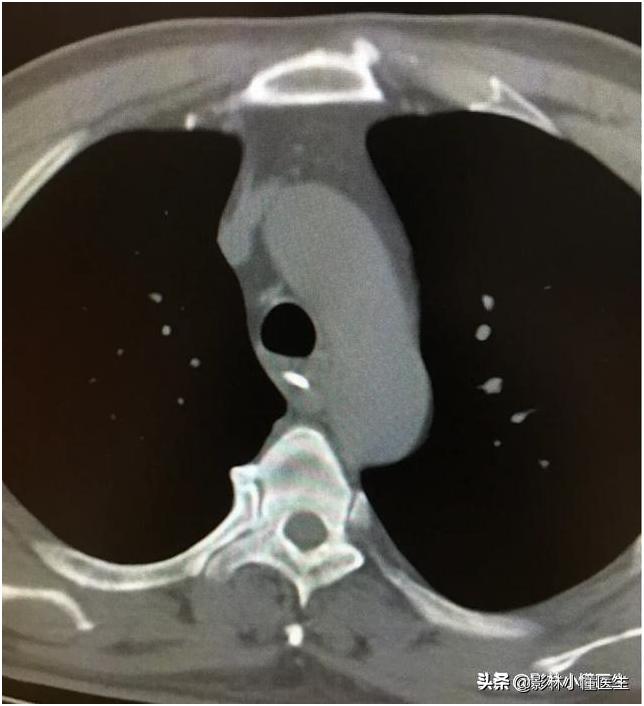

而CT检查则可以看到明确的食管异物以及位置,包括异物的长度、走形以及毗邻结构情况。

食管内见高密度影

异物平行于食道

患者做了吞钡检查后行CT检查明确周围结构情况

增强扫描有助于判断跟周围血管关系